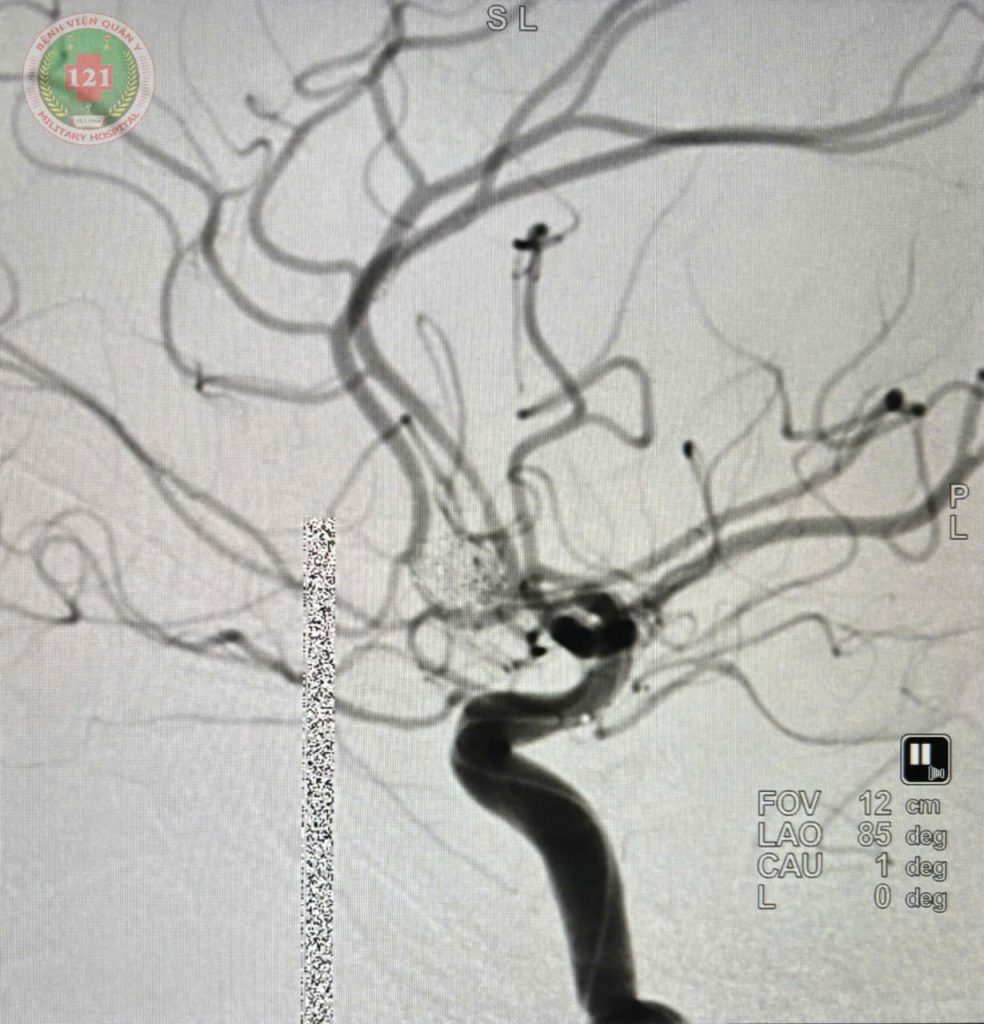

Với sự hỗ trợ chuyên môn từ Bệnh viện SIS Cần Thơ, ngày 28/01 Bệnh viện Quân y 121 đã thực hiện thành công ca can thiệp nút túi phình động mạch não cho một nam bệnh nhân 53 tuổi. Cách nhập viện 01 ngày bệnh nhân đột ngột xuất hiện tình trạng đau đầu dữ dội, buồn nôn và nôn nhiều, mặc dù đã dùng thuốc giảm đau nhưng không thuyên giảm nên đến khám và nhập viện tại Khoa Ngoạt thần kinh, Bệnh viện Quân y 121. Sau khi được các bác sĩ hội chẩn và tiến hành chụp cắt lớp vi tính mạch máu não (CTA: Computed Tomographic Angiography), kết luận bệnh nhân bị xuất huyết dưới nhện do vỡ túi phình động mạch thông trước, có chỉ định can thiệp nút túi phình cho bệnh nhân bằng vòng xoắn kim loại (Coil).

Nhờ sự phối hợp chặt chẽ giữa đội ngũ bác sĩ Bệnh viện Quân y 121 và sự hỗ trợ kỹ thuật từ Bệnh viện SIS Cần Thơ, sau 02 giờ ca can thiệp đã thành công tốt đẹp, đảm bảo an toàn và tuân thủ đúng quy trình chuyên môn. Sau can thiệp đến ngày 30/01 bệnh nhân phục hồi, tiếp xúc tốt, vận động tứ chi bình thường, sinh hiệu ổn định.